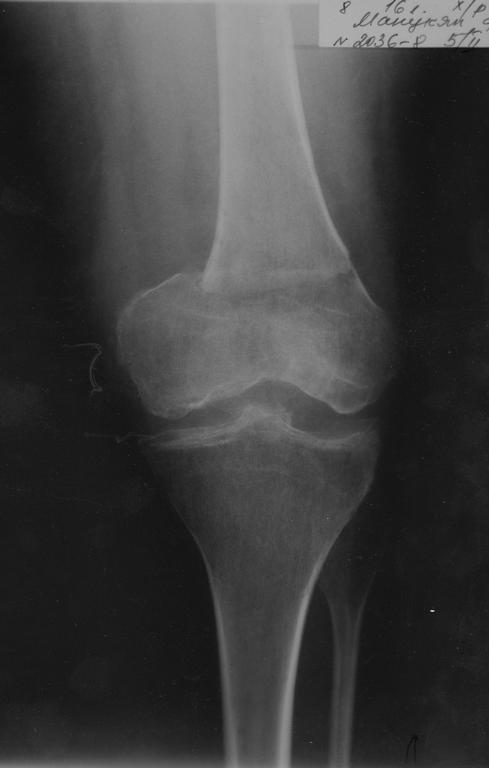

Вот недавний генген

Ситуация вряд ли может быть адекватно оценена по скудному непрофессиональному описанию. На снимке ничего тревожного не видно, можно движения разрабатывать. Препятствия разработке, скорее всего, обусловлены рубцовым процессом в мышцах. Возможно, и тем заболеванием, которое имелось.